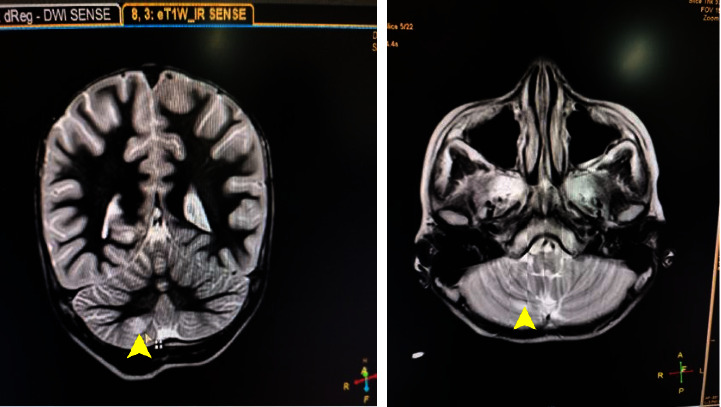

Background: Acute disseminated encephalomyelitis (ADEM) is a rare immune-mediated pathology involving inflammatory demyelination of the central nervous system. Case Presentation. In this case report, we present the case of a nine-year-old female who exhibited altered mental status and focal neurological deficit, subsequently diagnosed as ADEM based on clinical presentation and magnetic resonance imaging (MRI) findings. The patient was managed symptomatically along with glucocorticoids.

Conclusion: ADEM must be suspected when a patient, especially a child, presents with prodromal symptoms followed by multifocal neurological symptoms. Diagnosis can be established with an MRI brain scan. Most patients respond to high-dose intravenous glucocorticoids.